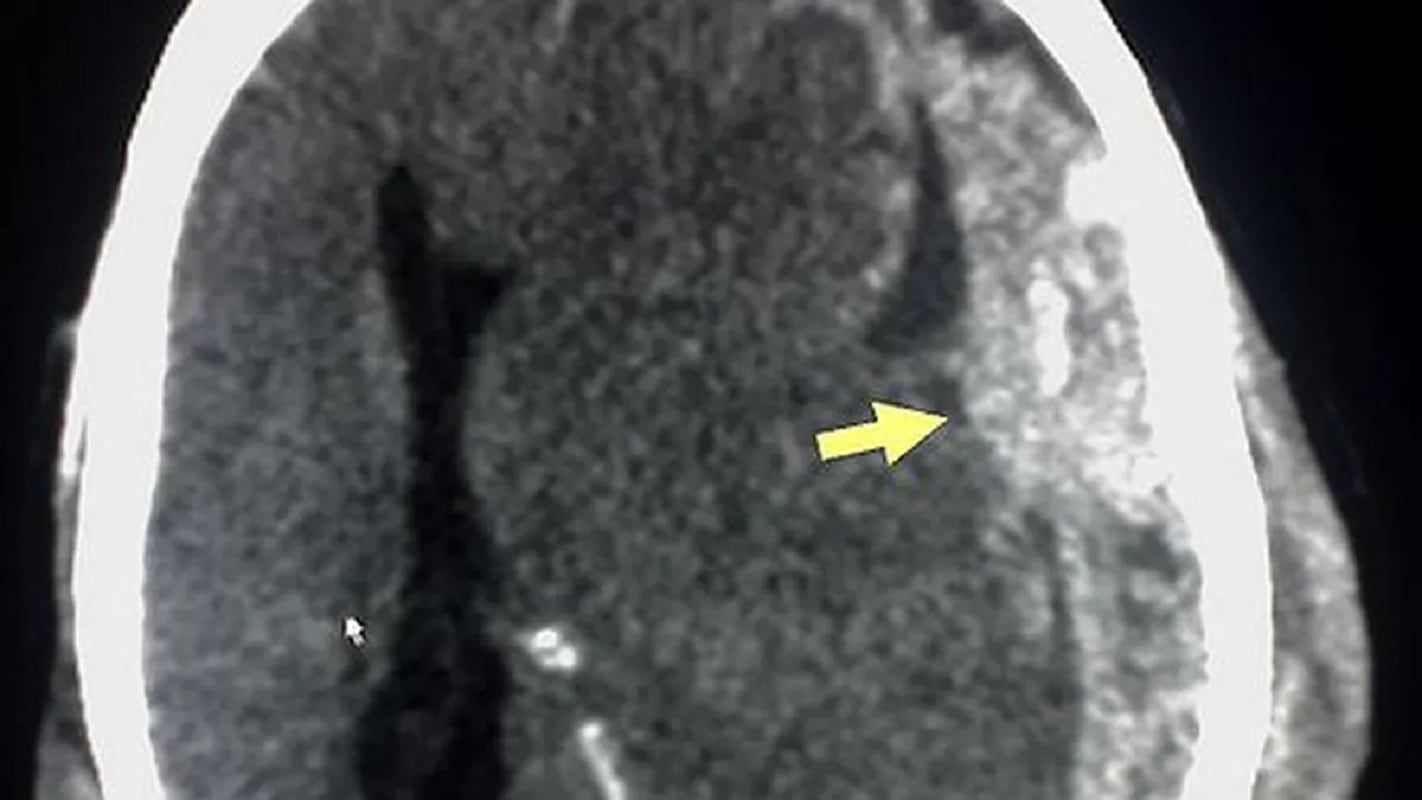

El mangaka Akira Toriyama falleció a los 68 años a causa de un hematoma subdural. Se trata de una acumulación de sangre entre las capas de tejido que recubren el cerebro.

El cerebro está protegido por tres capas de tejido llamadas meninges: la duramadre (la capa más externa y resistente), la aracnoides (una capa delgada en medio) y la piamadre (la capa más interna, que está en contacto directo con el cerebro). Entre la duramadre y la aracnoides hay un espacio llamado espacio subdural, el cual normalmente contiene solo una pequeña cantidad de líquido cerebroespinal.

Cuando ocurre un trauma en la cabeza, como un golpe o una caída, los vasos sanguíneos que atraviesan el espacio subdural pueden romperse, causando una acumulación de sangre. Este sangrado puede comprimir el tejido cerebral y causar una serie de síntomas, que van desde leves hasta potencialmente mortales, dependiendo del tamaño y la ubicación del hematoma.

Los hematomas subdurales se clasifican generalmente en agudos, subagudos o crónicos según la rapidez con la que se desarrollan los síntomas y la aparición del sangrado. Los hematomas agudos suelen ser el resultado de un trauma reciente y pueden causar síntomas graves rápidamente. Los subagudos tienen una progresión de síntomas más lenta, y los crónicos pueden desarrollarse durante semanas o meses.